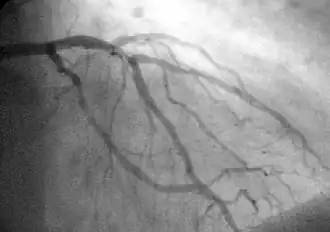

Een hartinfarct (medisch: myocardinfarct), in de volksmond hartaanval genoemd, is het proces waarbij een deel van de hartspier afsterft doordat de bloedtoevoer door de kransslagaderen naar dat deel van de hartspier wordt onderbroken. Een hartinfarct kan leiden tot hartfalen, sterfte of levensbedreigende ritmestoornissen. Een hartaanval ontstaat meestal doordat zich in een kransslagader een bloedstolsel oftewel een bloedpropje vormt waardoor de toevoer van bloed, die over het algemeen daarvoor al verminderd was, nu opeens helemaal wordt onderbroken. De blokkade ontstaat meestal op de plaats van een atherosclerotische plaque.

onderbroken bloedtoevoer in kransslagader